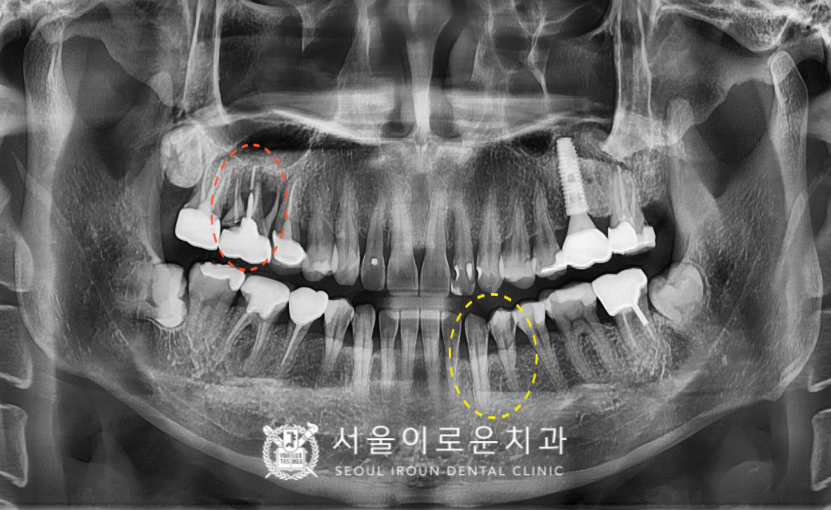

위턱 오른쪽 첫 번째 큰 어금니(#16)의

치아 뿌리 쪽으로 파절 되어있는 것을

확인할 수 있었고,

주변 잇몸뼈의 흡수가 심하고

동요도 또한 심한것을 체크할 수 있었습니다.

이 경우 살려 쓰기 어려울 것으로 판단되어

안타깝게도 발치가 필요한

상황이었습니다.

발치 후 임플란트를 고려해야 하는 상황인데,

뿌리 쪽 잇몸뼈의 흡수가 심해

남아 있는 뼈의 양도 작고,

상악동도 많이 내려와 있는 상황이었는데요.

그리고 불편감을 호소하신

오른쪽 위턱 어금니 외에도

왼쪽 아래턱 송곳니(#33)와

바로 뒤 첫 번째 작은 어금니(#34)는

치아 사이 부분에서 충치가 관찰되었는데요.